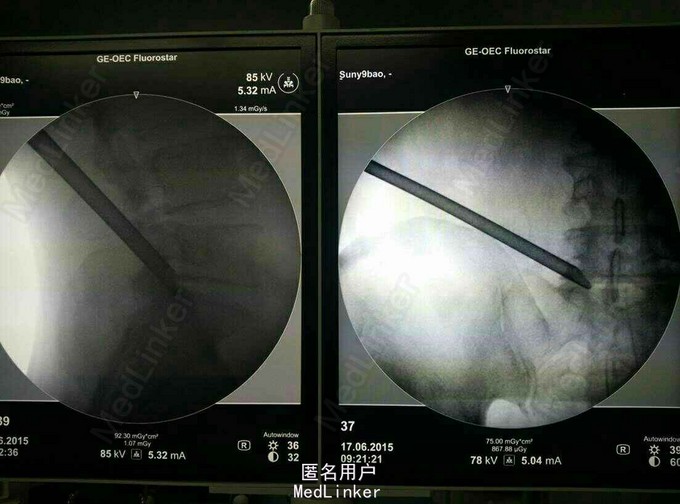

诊断:L45及L5/S1 双节段椎间盘突出(左侧),辅助检查:MRI提示: L45及L5/S1 双节段椎间盘突出,压迫左侧神经根。

术后症状立即缓解,术后两小时佩戴支具下地活动。